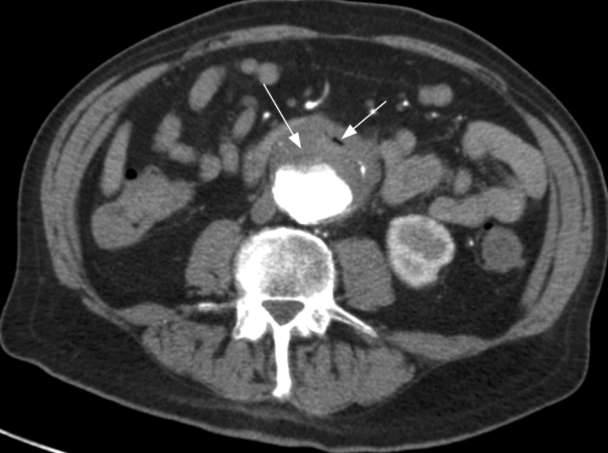

The Stanford classification of the dissection pictured here:

What is Type A?